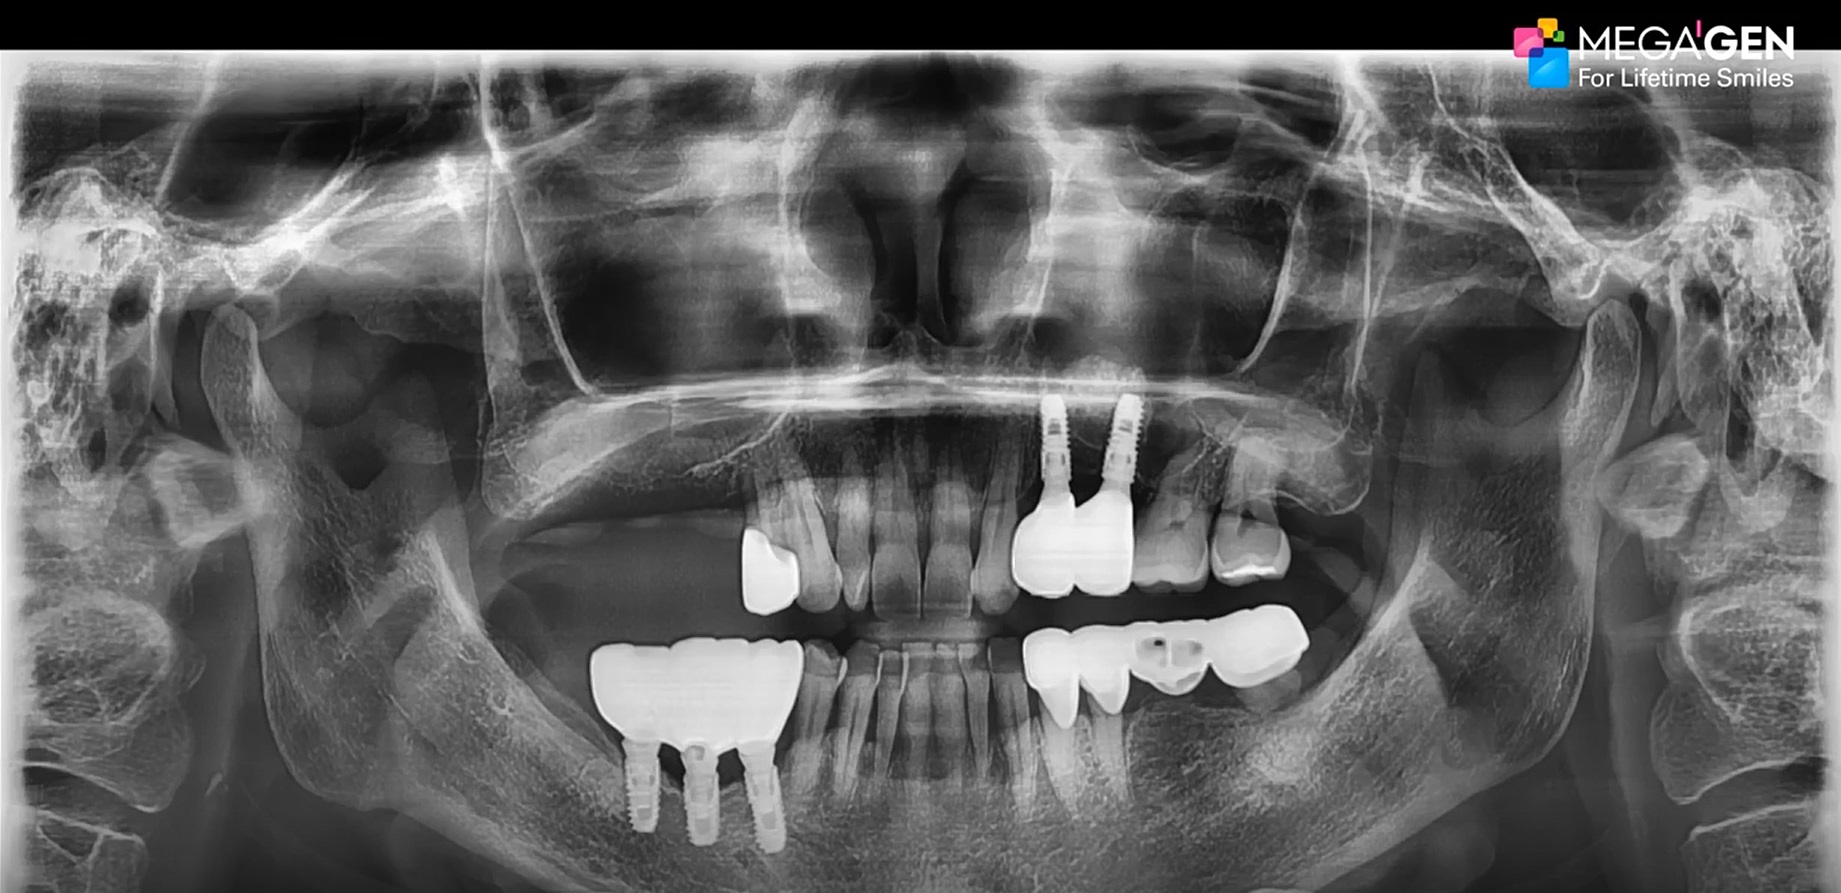

#11,#12,#23,#24 Root Membrane Technique with Digital R2GATE Surgery

Dr. Kwang Bum Park,Aesthetic zone,Digital Guided Surgery,Maxillary Anterior,Maxillary Posterior,#11,#12,#23,#24,Guided surgery,Root Membrane,AnyRidge,MiNi,R2GATE Guide,MEGA ISQ,Root Membrane Kit,R2GATE Surgical Kit(AnyRidge),Initial stability,Customized abutment,PMMA crown,Aesthetic…